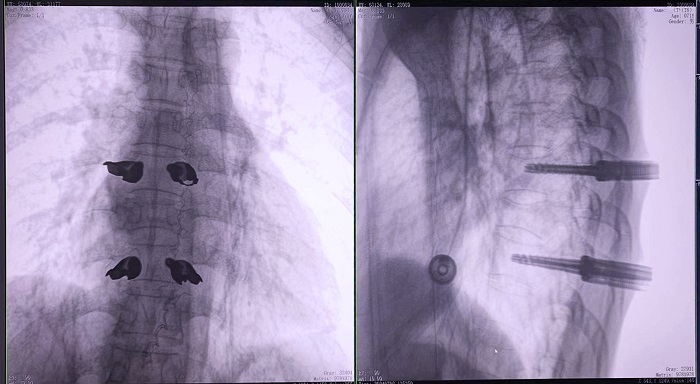

③機器人輔助胸椎手術操作難點之精準置釘

傳統開放手術中,胸椎的手術視野相對受限,螺釘的置入主要依賴于醫生的經驗和手感,存在一定的主觀性。

普愛醫療手術導航定位系統解決方案

普愛醫療骨科手術機器人的高精度機械臂,按照規劃好的路徑及角度,自動精準定位穿刺點,醫生打入克氏針后,正側位圖像顯示精度滿足預期,醫生完成置釘等后續手術操作。